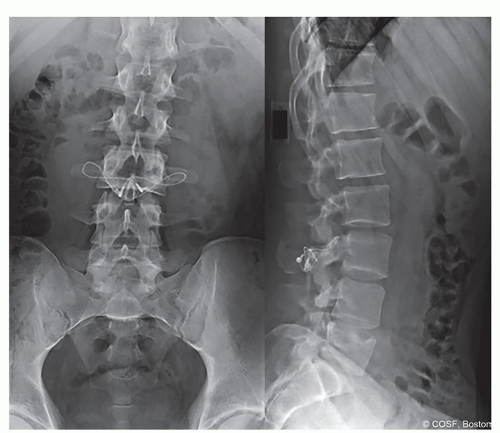

Figure 7-4 ▪ Pedicle screw plus wiring MR4201677. (Courtesy of Children’s Orthopaedic Surgery Foundation.)

Pedicle screw

Place bilateral polyaxial pedicle screws avoiding facet joint

Decorticate base of TP and lamina

Insert bone graft into pars defect, base of TP, and lamina

Implant secured to posterior process. Implant options:

Contour 4.5 mm rod in “U” shape passed rod inferior to L5 spinous process

Polyethylene cord instead of rod (physician directed use, not FDA approved)

Wire

Insert rod into pedicle screw head and compress